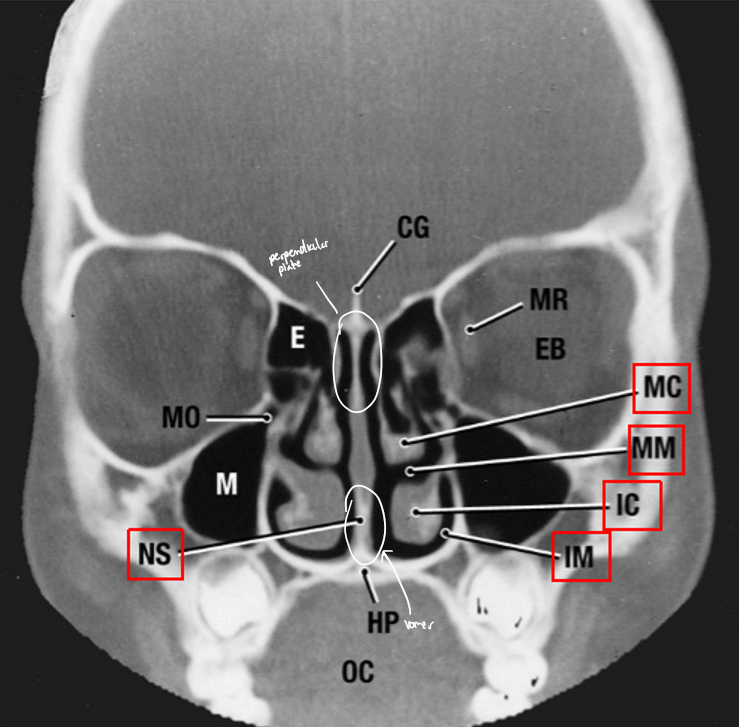

CG: Crista galli

NS: Nasal septum

EB: Eyeball

MR: Medial rectus

E: Ethmoid air cell

M: Maxillary sinus

HP: Hard palate

OC: Oral cavity

MC: Middle concha

MM: Middle meatus

IC: Inferior concha

IM: Inferior meatus

The ______ is not part of the ethmoid

inferior concha